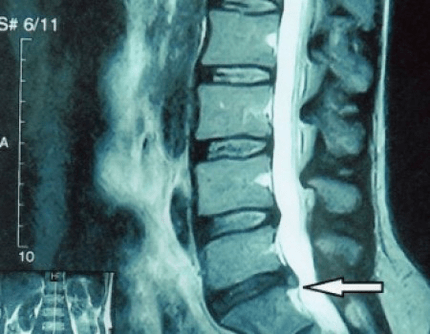

protrusão de um disco espinhal em uma ressonância magnética

Por que isso aconteceu? Com o tempo, o anel fibroso desgasta-se gradualmente. Ele não pode mais esticar, apenas se projeta para fora, além do disco, ou quebra. O núcleo para de transmitir e transformar carga vertical em carga radial. Com a idade, o estresse se acumula gradualmente dentro dos discos e sua estrutura muda. Se todos esses processos, tomados em um disco separado, forem transferidos para toda a coluna vertebral, teremos na clínica uma condição chamada osteocondrose. Agora podemos começar a definir.